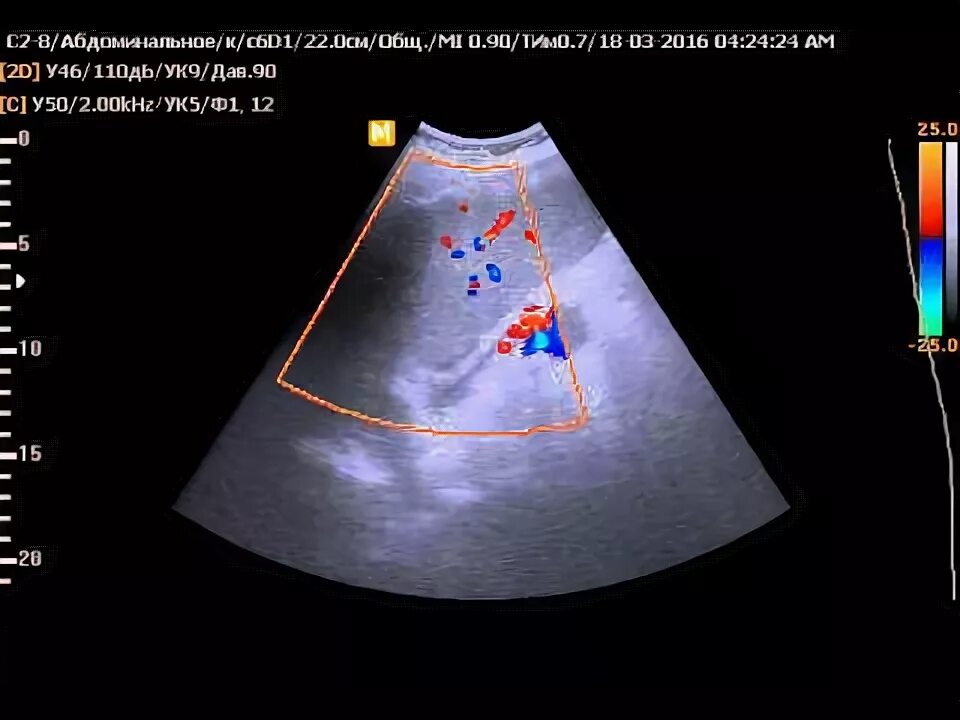

Асцит в малом тазу